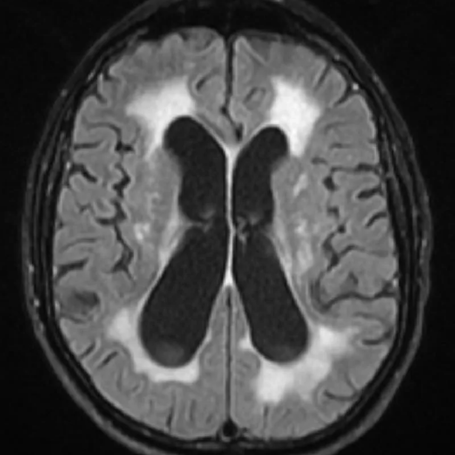

Hidrocefalia de presión normal

Tipos: La hidrocefalia de presión normal (HPN) es un tipo de hidrocefalia comunicante que se caracteriza por presentar los signos y síntomas clásicos de hidrocefalia pero con una tomografía relativamente normal. Suele presentarse en adultos mayores.

Diagnóstico: Se basa en la triada clásica: alteración de la marcha (marcha magnética), deterioro cognitivo, e incontinencia urinaria. Se confirma pruebas como la punción lumbar para evaluar respuesta al drenaje de LCR.